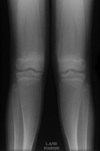

43

Give 3 differentials in order of likelihood.

(Erlenmeyer flask deformity) 1. Thalassemia 2. Sickle cell anemia 3. Osteopetrosis

44

Give 2 differentials in order of likelihood.

1. Thalassemia 2. Sickle cell anemia